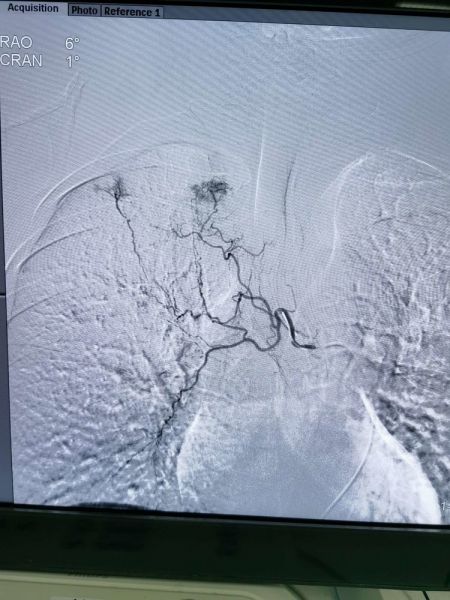

左上支气管动脉与出血病灶动脉交通

用栓塞微粒球+PVA+弹簧圈三明治方法栓塞满意,手术历时一小时四十分钟,共栓塞三支犯罪血管,元月31日康复出院。